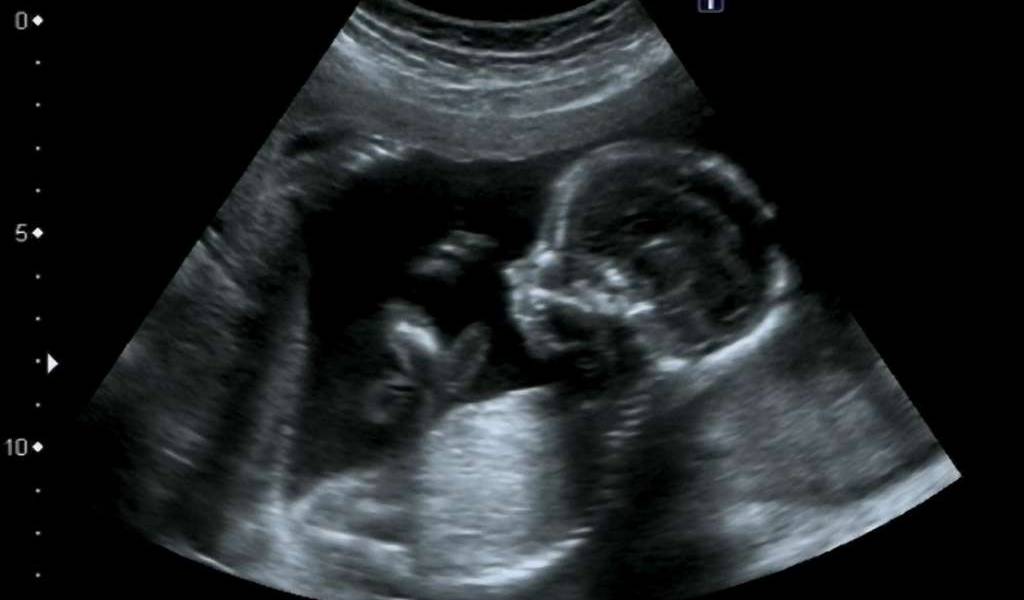

El mostrar el más mínimo detalle del bebé no se podía lograr en la antigüedad. Foto referencial / Larazon.es

Con las modernas ecografías, el que la madre vea cómo se va desarrollando el bebé en su vientre, es mucho más especial, ya que los nuevos equipos capturan imágenes del feto a velocidad real y en alta resolución, como si la mujer tuviera una cámara dentro del útero.

Con esto, también se ha captado muchos gestos y movimientos del pequeño, algo que no se podía hacer en la antigüedad.